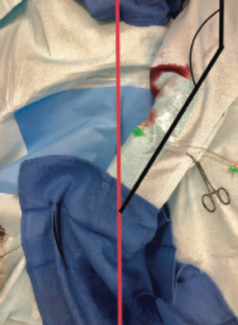

Richard Casazza, MAS

Here, we describe the “Peek-a-Boo” technique, designed to offer an ergonomic left radial solution for operators who still have reservations regarding use of a distal approach. This technique is extremely easy, effective, and ergonomic. It can...